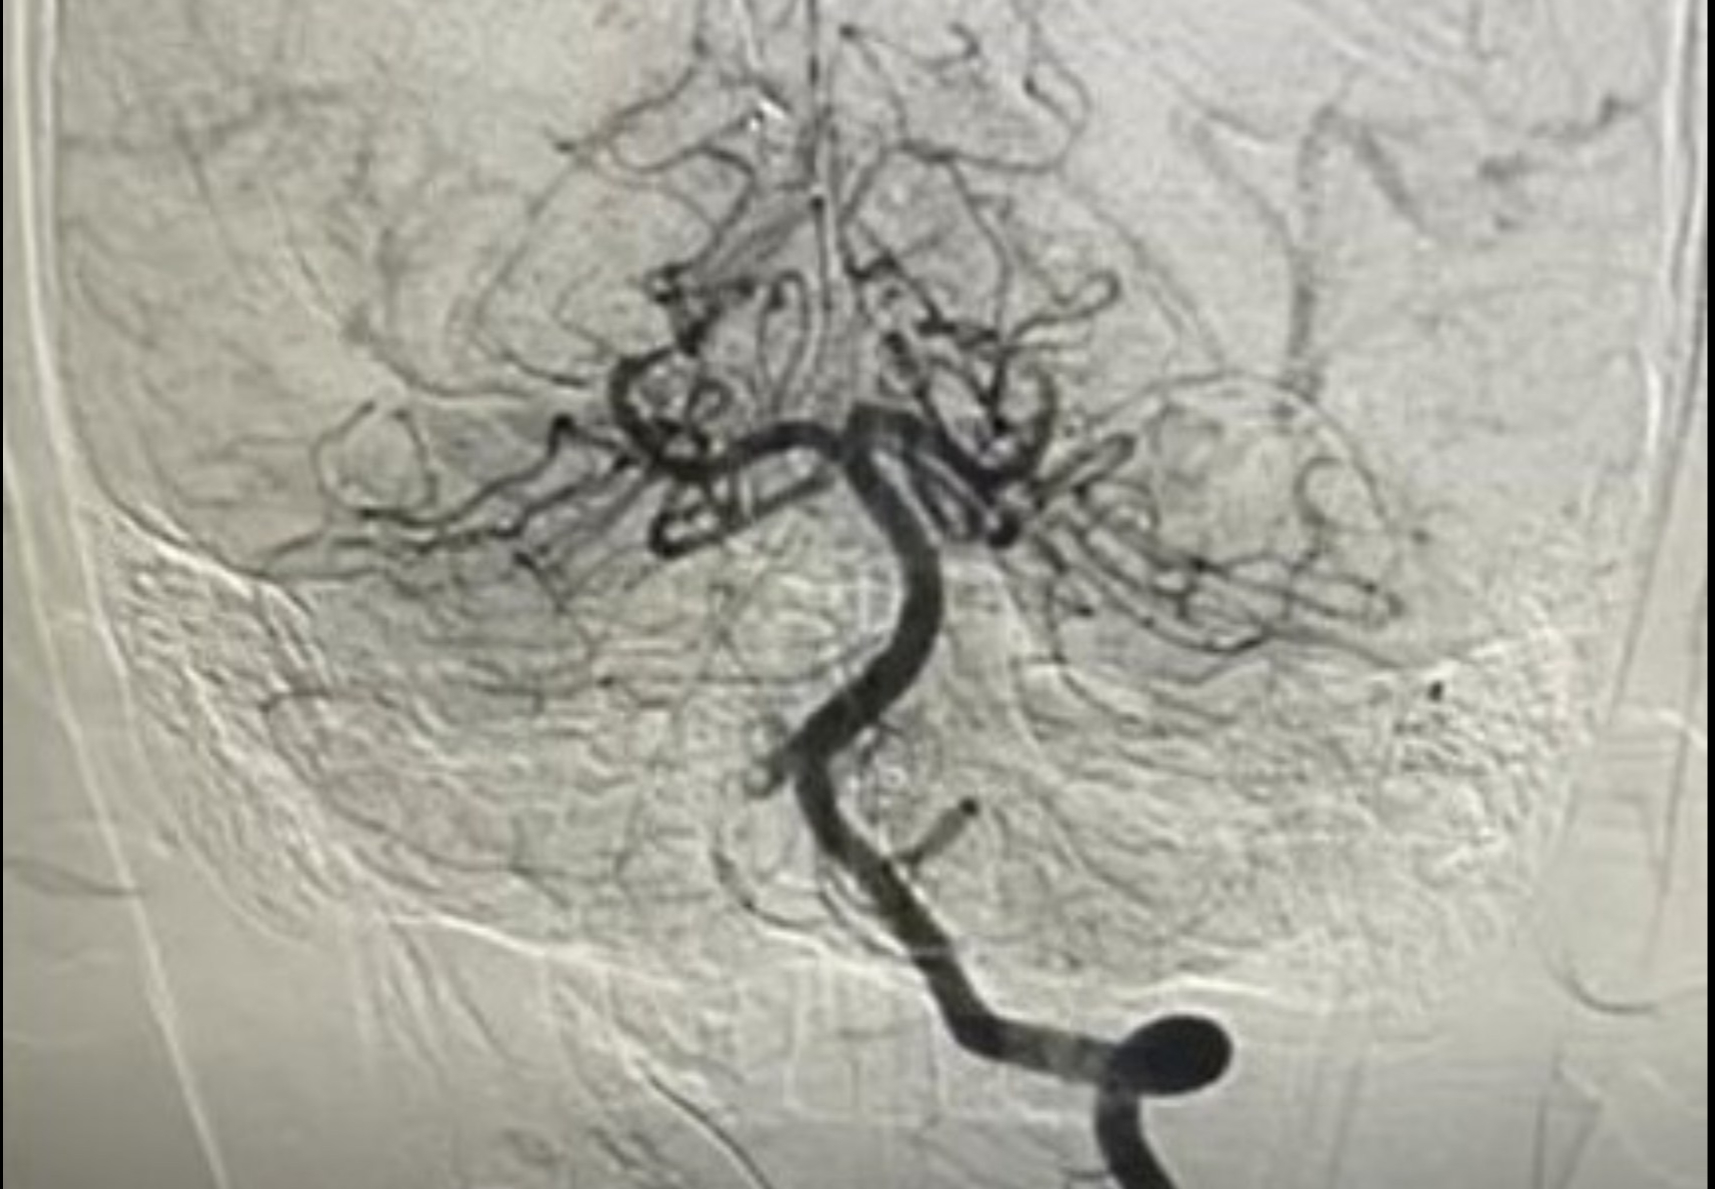

Ảnh chụp mạch máu xóa nền DSA của bệnh nhi 10 tuổi bị nhồi máu não cấp - Ảnh: Bệnh viện cung cấp

Khi can thiệp càng sớm, tỉ lệ biến chứng và tử vong càng thấp. Vì vậy bệnh nhi cần chẩn đoán sớm bằng cách dựa vào triệu chứng lâm sàng, hình ảnh MRI não, MRI mạch máu não (CT chỉ để loại trừ xuất huyết ban đầu) và một số xét nghiệm tầm soát.